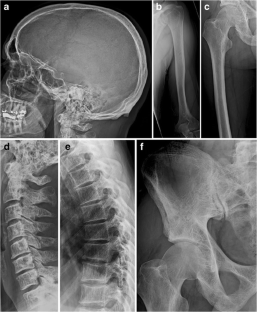

Radiographic findings in Waldenström’s macroglobulinemia resembling fibrogenesis imperfecta ossium (FIO): A case report

A case of Waldenström’s macroglobulinemia with radiographic features of fibrogenesis imperfecta ossium is presented. The case raises the possibility that these radiographic findings might be more common in Waldenström’s macroglobulinemia than previously appreciated, and illustrates the need for bone biopsy to establish a definitive diagnosis of fibrogenesis imperfecta ossium.

Fig. 1

Fig. 2

Fig. 3